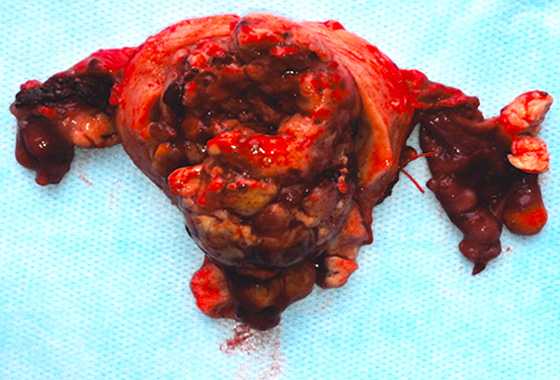

Через 2 месяца после УЗИ и МРТ пациентке выполнено хирургическое лечение в объеме экстирпации матки с придатками (рис. 3). По результатам морфологического исследования материалов операции опухоль сформирована из клеток веретенообразной формы, собранных в переплетающихся в различных направлениях пучки (рис. 4.). Клетки опухоли вытянуты по полюсам с веретенообразным центрорасположенным ядром, структура хроматина мелкоглыбчатая. Отмечался пикноз отдельных ядер, вакуолизация цитоплазмы, некоторый ядерный клеточный полиморфизм. Митозы в поле зрения. Каждая клетка была погружена в волокнистую строму. Строма опухоли с явлениями отека, отмечается присутствие тучных клеток, а также эозинофильных лейкоцитов, зрелых лимфоцитов, локализующихся преимущественно периваскулярно. Сосуды щелевидные. Таким образом, был выставлен окончательный диагноз: миома с выраженными дегенеративно-дистрофическими изменениями.

Рисунок 3. Макропрепарат: удаленная матка с придатками. Полость матки вскрыта, в просвете −

экзофитная крупнодольчатая опухоль на широком основании с признаками нарушения питания, кровоизлияниями, отеком.